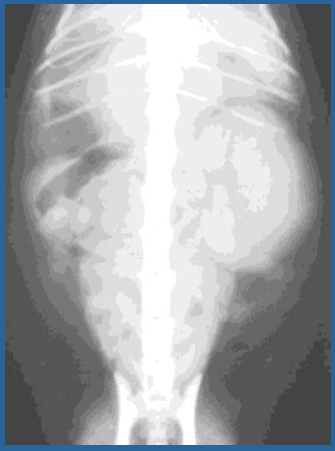

Progressive Dilation of the Renal Pelvis and Atrophy of the Renal Parenchyma

Hydronephrosis

Clinical Signs of which Kidney Disease:

*Kidney will Feel like a Tumor Mass- Palpable Mass

How do we Diagnose Hydronephrosis?

Abdominal Radiographs

Ultrasound

Excreatory Urogram